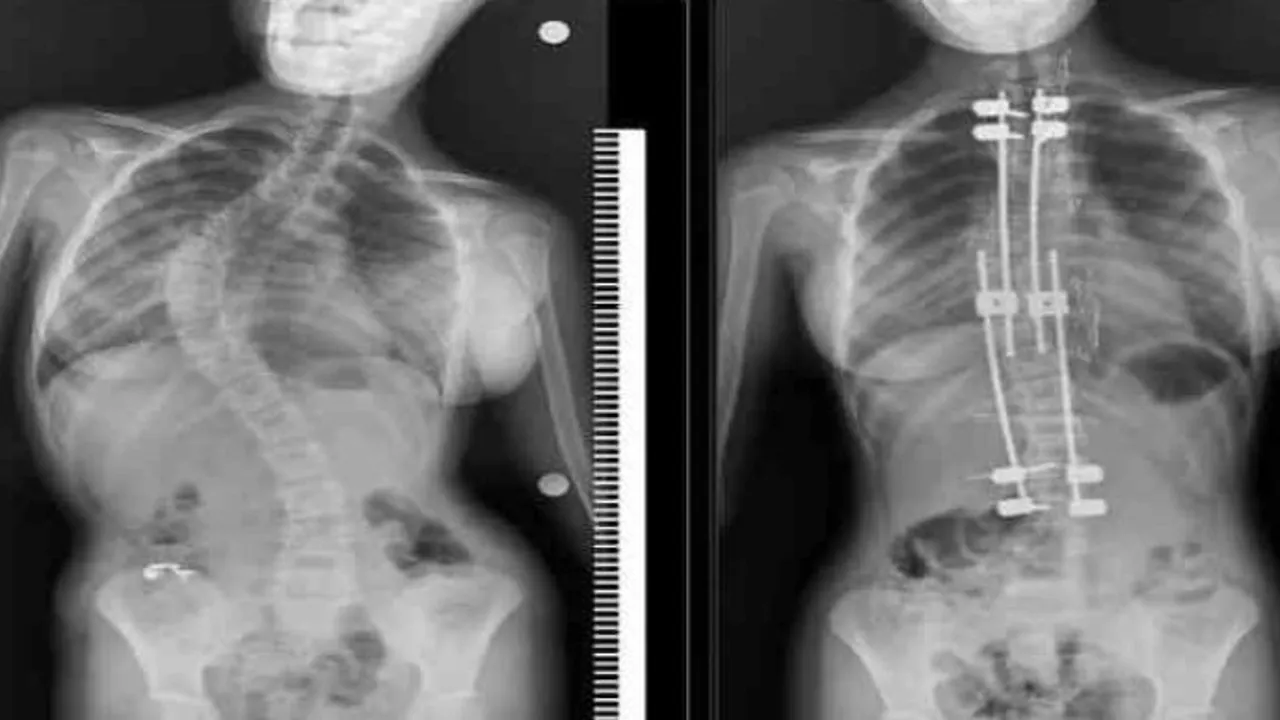

Samsun'un Bafra ilçesinde yaşayan 10 yaşındaki Zümra Demircioğlu bel ve sırt bölgesinde aşırı ağrı ve günlük aktivitelerini yapmakta zorlanma şikayetleri nedenleriyle Samsun Eğitim ve Araştırma Hastanesi'ne başvurdu. Burada çekilen röntgen ve yapılan tetkikler sonucunda 75 derece omurga eğriliği tespit edilen minik Zümra için ameliyat kararı verildi. Büyüme koruyucu sisteminin uygulandığı ameliyatta minik Zümra'nın omurgası düzeltildi. Özel hastanelerde ortalama 300 ile 500 bin TL arasında yapıldığı öğrenilen bu ameliyat artık Samsun Eğitim ve Araştırma Hastanesi'nde ücretsiz olarak gerçekleştiriliyor.

Ameliyat hakkında bilgi veren Dr. Ömer Bozduman, "Bu gibi durumlarda uzayan rot dediğimiz bir sistem uyguluyoruz. Bunun nedeni çocukları yaşı küçük olduğu için füzyon dediğimiz kaynatma ameliyatı yaparsak akciğerlerinde yetersiz gelişme, göğüs kafeslerinde yetersiz gelişme ve kanallarında yetersiz gelişme oluşabileceği için büyüme koruyucu cerrahi yapıyoruz. Büyüme koruyucu cerrahinin diğer füzyon cerrahisinden alternatifi şudur: Düzenli aralıklarla düzeltme yapıyoruz. Çocuk büyüdükçe biz de bu sistem anestezi altında ya da anestezisiz olarak uzatarak çocuğun yeterli omurga büyüklüğüne ulaştıktan sonra yeterli kalıcı ameliyatı gerçekleştiriyoruz. Anestezi hocamız Doç. Dr. Serkan Turgal yardımı ile bu ameliyatı başarıyla gerçekleştirdik. 10 yaşındaki hastamıza büyüme koruyucu sistemi yerleştirdik. Düzenli aralıklarla uzatmalarını yapacağız. Nihai ameliyatını omurgası büyüdükten sonra gerçekleştireceğiz. Eğitim ve Araştırma Hastanesi olarak bir ilki gerçekleştirdik. Hastamız gayet iyidir. Birinci günün kalkıp yürüdü. Dördün gün sonra taburcu ettik. Herhangi bir nörolojik veya başka bir sorunla karşılaşmadık. İhtiyacı olan tüm hastalarımıza Samsun Eğitim ve Araştırma Hastanesi olarak devletimizin imkanlarıyla bu hizmeti ücretsiz olarak veriyoruz. Aileler bu semptomlar hakkında dikkatli olmalıdır. En ufak şüphede polikliniklerimize bekliyoruz. Bizler yardımcı olacağız" diye konuştu.